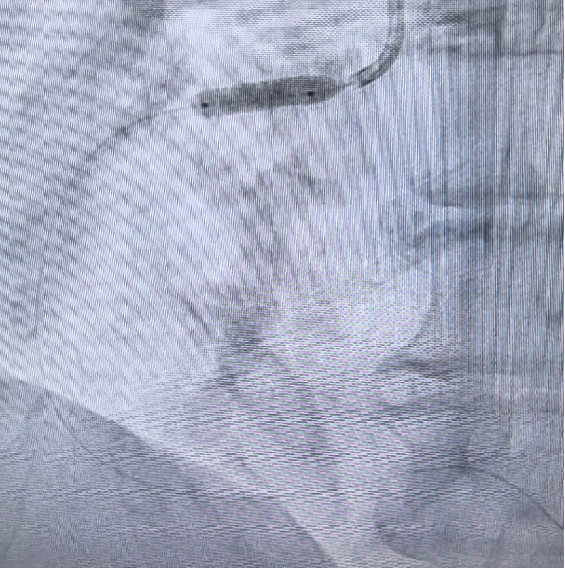

左图:导引导丝尝试后进入,患者胸闷明显,频发室早,放弃 IVUS,直接 20-15 FLEX 球囊 POBA。

右图:4.0-15 DES 植入。

DES 植入后 RCA 开口处一细小分支受压闭塞,患者胸痛。

4.5-12NC 球囊后扩张后 PILOT 50 及 XT 反复尝试无法进入闭塞分支。对症处理后,患者症状减轻。